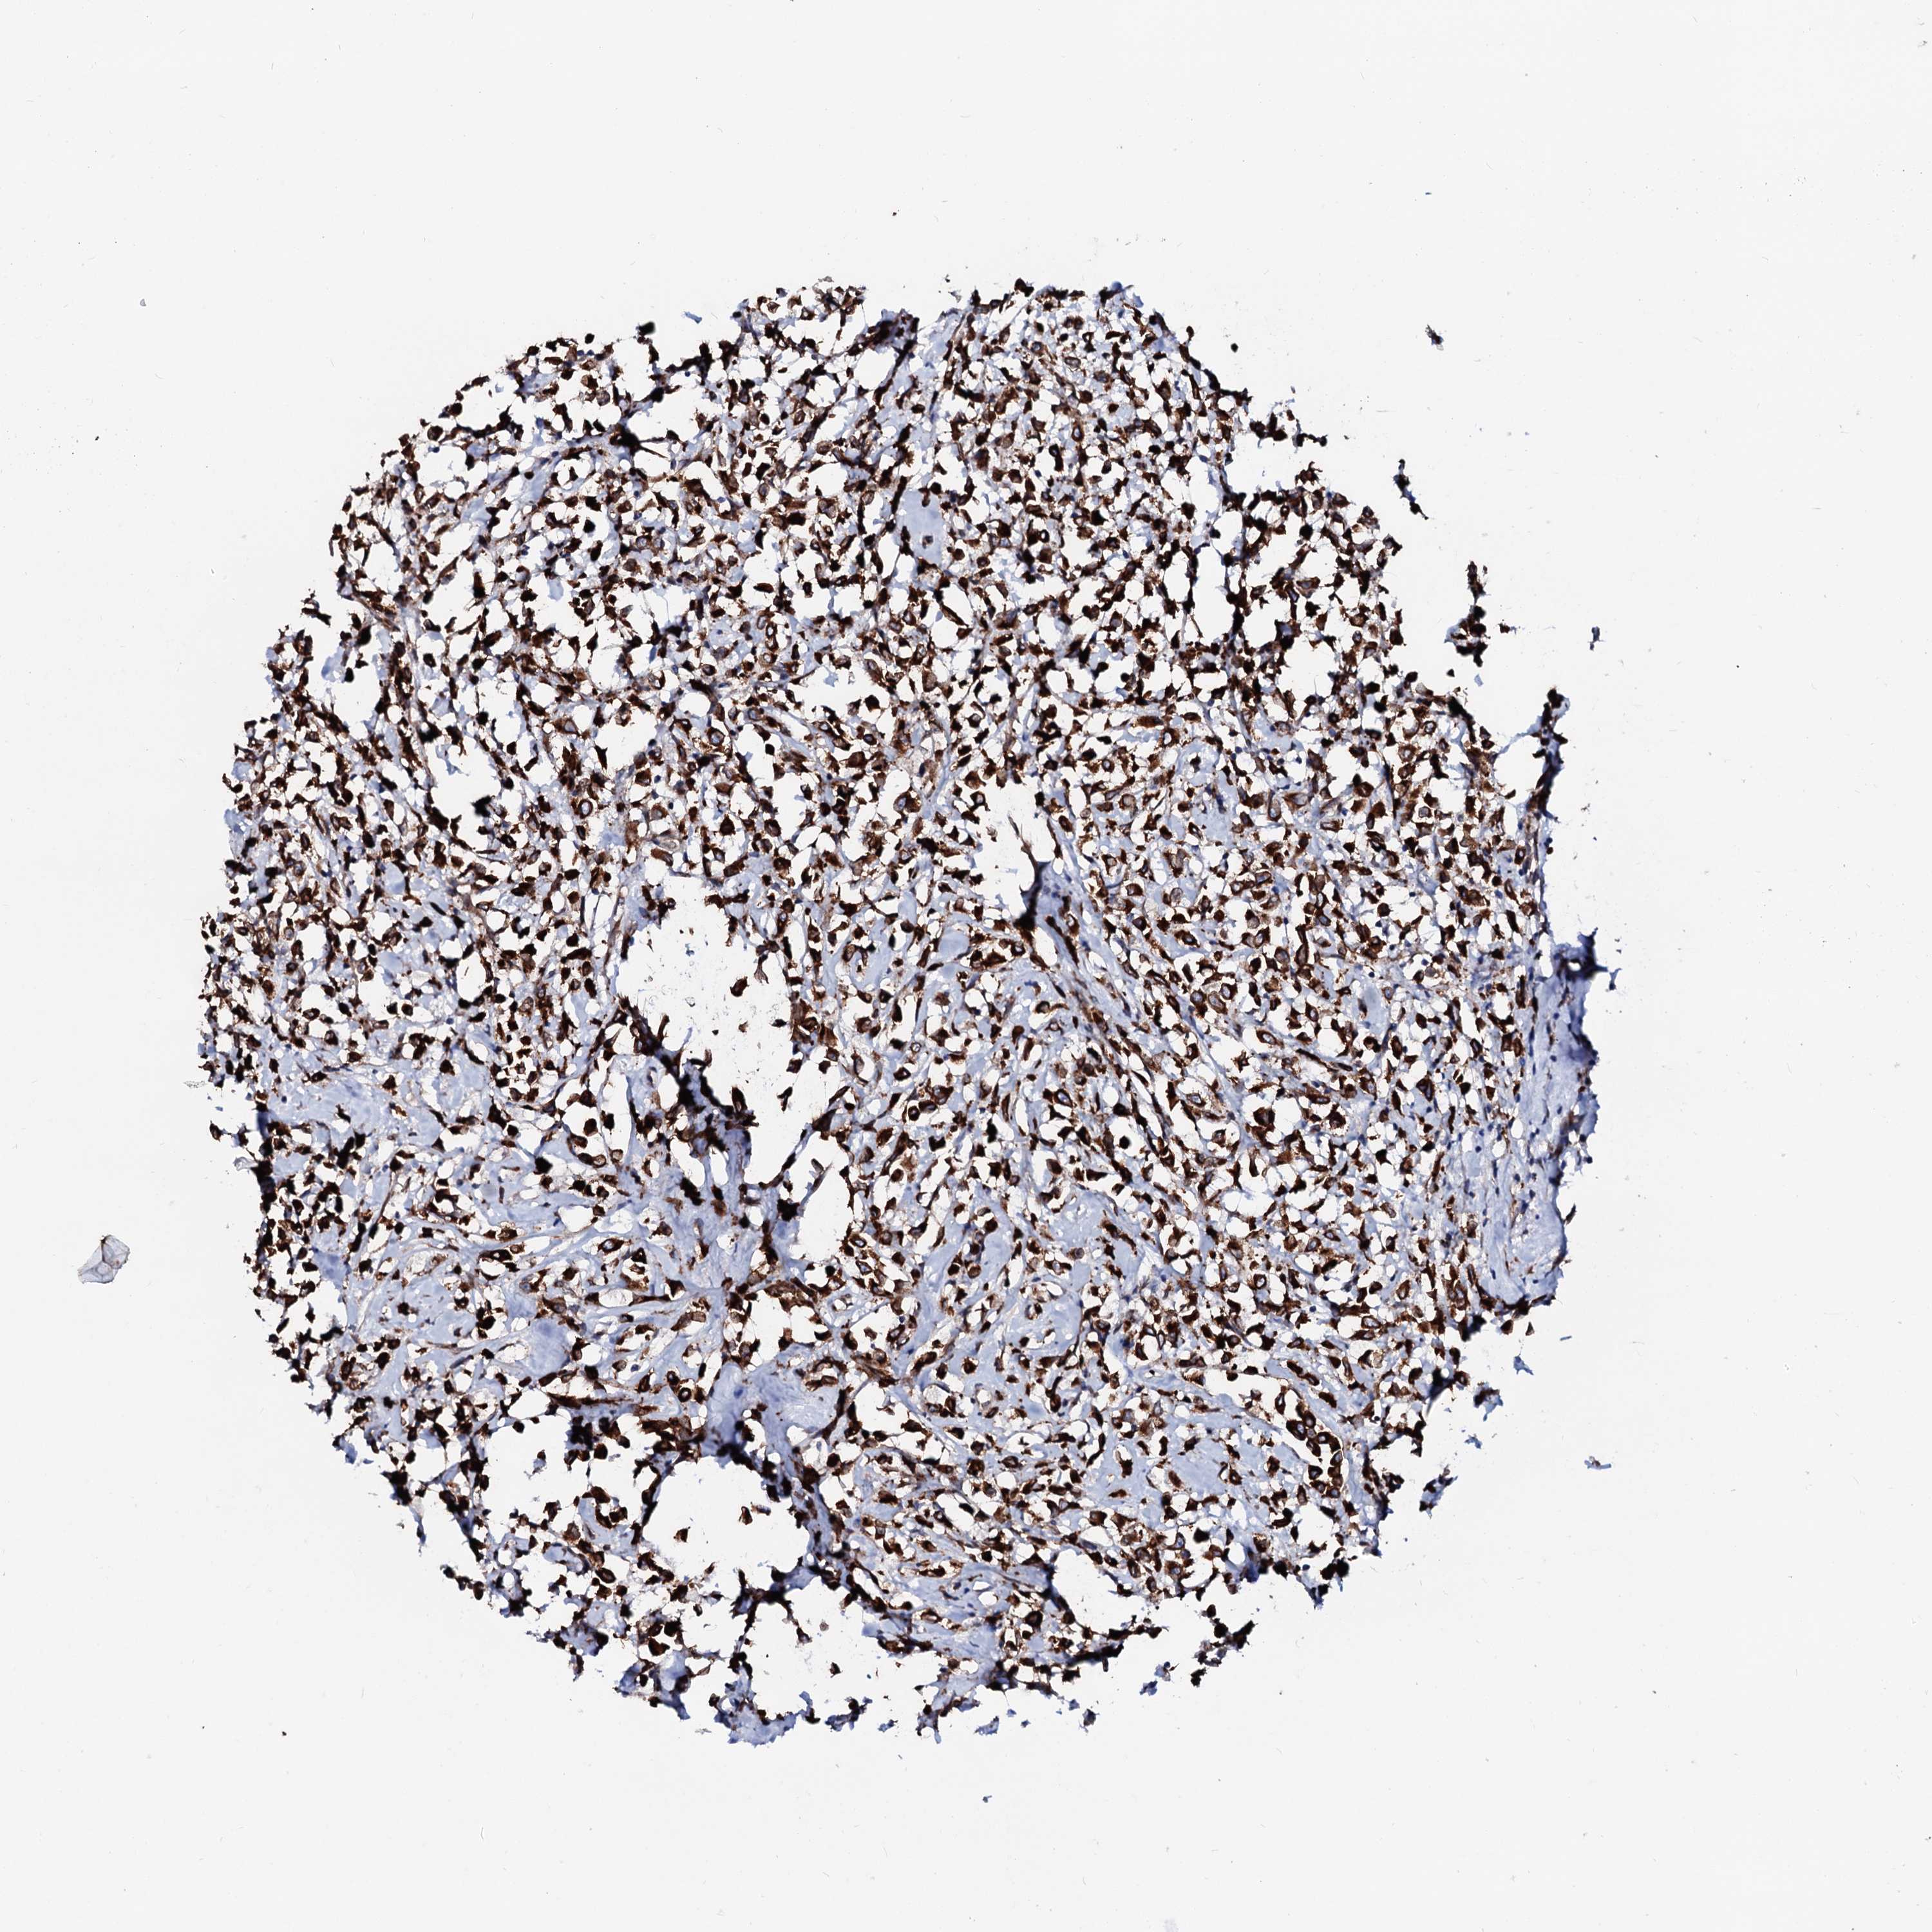

CANCER BREAST CANCER Show tissue menu

BRCA TCGA BRCA VALIDATION PROTEIN EXPRESSION